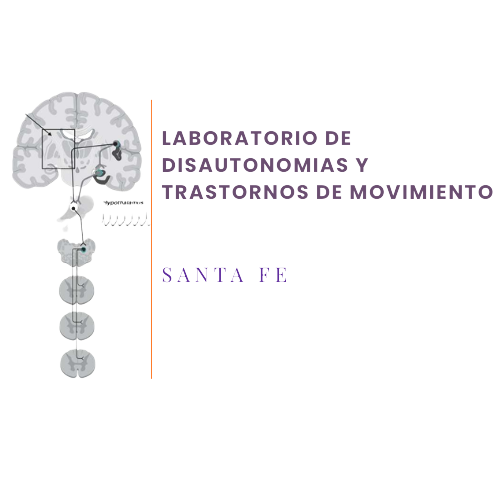

¿Qué sistema se evalúa?

Evaluación de los reflejos simpáticos cardiovasculares en reposo y bajo estrés.

Evaluación de los síntomas sistémicos de disfunción autonómica, incluyendo la sudoración, la función digestiva, la regulación de la temperatura y la respuesta del flujo sanguíneo cerebral durante la inclinación activa y pasiva.

¿En quién está indicada la evaluación del sistema nervioso autónomo?

Evaluamos a personas que presentan debilidad, mareo, palpitaciones, fatiga o intolerancia al esfuerzo físico. Estos síntomas se clasifican como intolerancia ortostática.

También evaluamos a pacientes con síntomas persistentes sin un diagnóstico claro, así como a aquellos diagnosticados con fibromialgia o síndrome de fatiga crónica.

Evaluamos a pacientes con síntomas sensoriales o motores relacionados con trastornos neurológicos funcionales.

Brindamos apoyo a pacientes que han consultado a múltiples especialistas y se han sometido a diversas pruebas o tratamientos sin obtener un diagnóstico claro